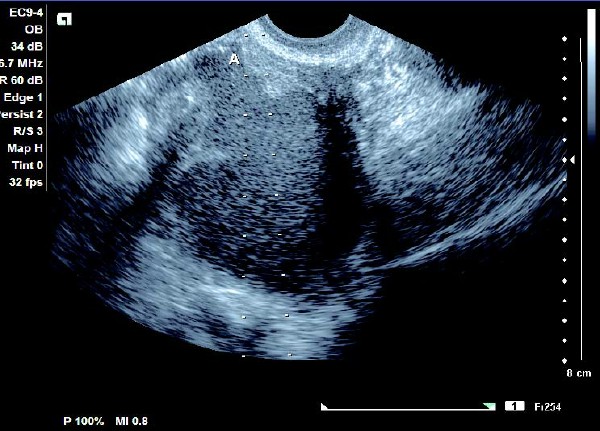

卵巢巧克力囊肿彩超描述,卵巢巧克力囊肿的超声诊断要点 3.囊内团块型:呈无回声区,囊内有散在细小光点及单个或多个高回声光团,形态规则。CDFI 检测:囊壁可见条状血流信号,高回声光团无血流信号。

卵巢巧克力囊肿彩超描述,卵巢巧克力囊肿的超声诊断要点 4.混合型 肿块为囊实相间的杂乱回声,囊腔内充满细小强回声光点、光班、光团或光带分隔,后壁界线较模糊。CDFI 检测:囊壁或光带有条状血流信号。

患者,女,35岁。每次月经量少,痛经,近来行经期延长、疼痛加重来院诊治。超声报告显示子宫前倾位,子宫体大小为:5.9cm×5.1cm×4.8cm,形态规则,边界清晰,宫避回声匀称,宫腔线居中,内膜厚度0.6cm,宫内未见异常回声。右侧卵巢内可见大小约5.2 cm×4.9cm的无回声区暗区,壁厚,内壁欠光滑,内见密集细光点,边界清晰。CDFI探测囊壁及囊腔内无血流信号。

超声提示:右侧卵巢巧克力囊肿